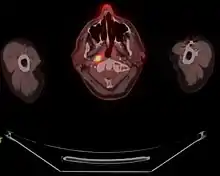

FDG-PET/CT scan of a patient with nasopharyngeal cancer. Transverse slice demonstrating FDG-positive primary site

Staging of nasopharyngeal carcinoma is based on clinical and radiologic examination. Most patients present with Stage III or IV disease.